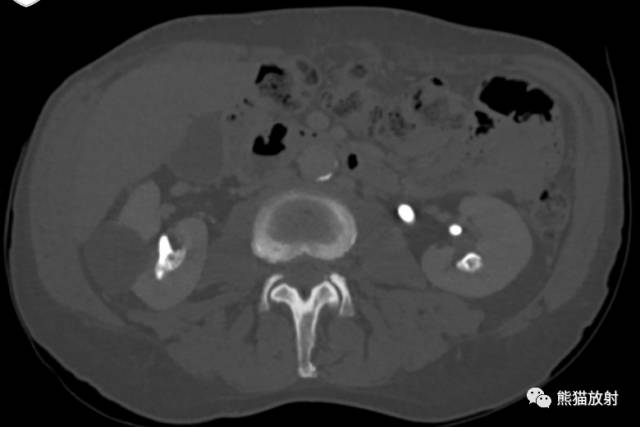

CT urogram (2017): Noncontrast images demonstrate multiple bilateral nonobstructing renal calculi, the largest measuring 6 mm in the right kidney. Some of the calcifications could represent nephrocalcinosis — for example, those in the upper pole of the right kidney. The kidneys show symmetric enhancement without suspicious renal mass. Multiple bilateral exophytic simple renal cysts are noted, the largest in the midpole of the right kidney measuring 3.6 x 4.3 cm. There are additional subcentimeter low-attenuation lesions that are too small to characterize. There is a “paintbrush sign” appearance to the renal medullae in keeping with a history of medullary sponge kidney. There is mild bladder wall thickening and trabeculation that may be related to chronic outlet obstruction. Further evaluation is deferred to cystoscopy.

CTU:CT平扫可见双肾多发非梗阻性肾结石,右肾最大者直径约6mm,其中一些钙化可能代表肾结石,例如,右肾上极的那些。肾脏对称性强化,未见可疑肾肿物。双肾可见多发单纯性肾囊肿,大者位于右肾中部,大小约3.6 x 4.3 cm;另可见不足1cm的低密度灶,其太小而不能显示。肾髓质表现为“毛刷征”,符合髓质海绵肾。膀胱壁轻度增厚并小梁形成,与慢性流出道梗阻有关。进一步评估需膀胱镜检查。